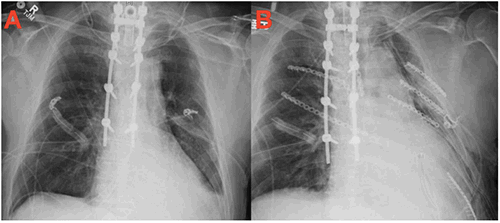

Figure 2: Figure 2A depicts an anterior-posterior preoperative chest x-ray and Figure 2B depicts an anterior-posterior postoperative chest x-ray following rib fixation.

The patient was then rotated into the lateral oblique position, re-draped, and several displaced fractures of the lateral left ribs 4, 5, 6, and 8 were openly reduced and internally fixated via a muscle-sparing thoracotomy through a lazy S incision (Figure 5 and Figure 6). Titanium plates were successfully used to fixate the fractures, as evidenced by the patient’s preoperative and postoperative X rays in Figure 2A and Figure 2B, respectively. Depth-controlled drilling technology was applied to avoid retro-mediastinal injury. The patient required placement of a tracheostomy and was on a ventilator for 12 days following the procedure. As a result of the intervention, the patient’s respiratory conditions improved, which contributed to his successful rehabilitation and the minimization of other morbidities from the trauma.